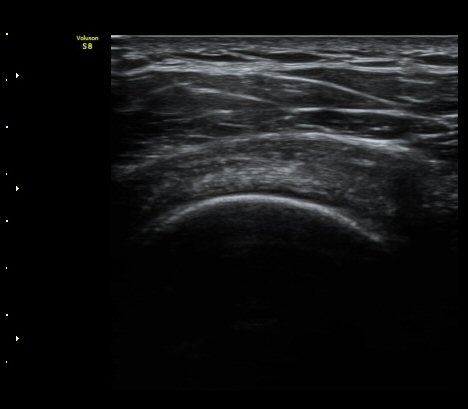

°ß°©ÇÏ±Ù°Ç Á¾´Ü¸é°Ë»ç¿¡¼­ ƯÀÌ ¼Ò°ß ¾øÀ½

(no specific abnormal findngs with longitudinal scan of subscapularis tendon) »çÁø 3